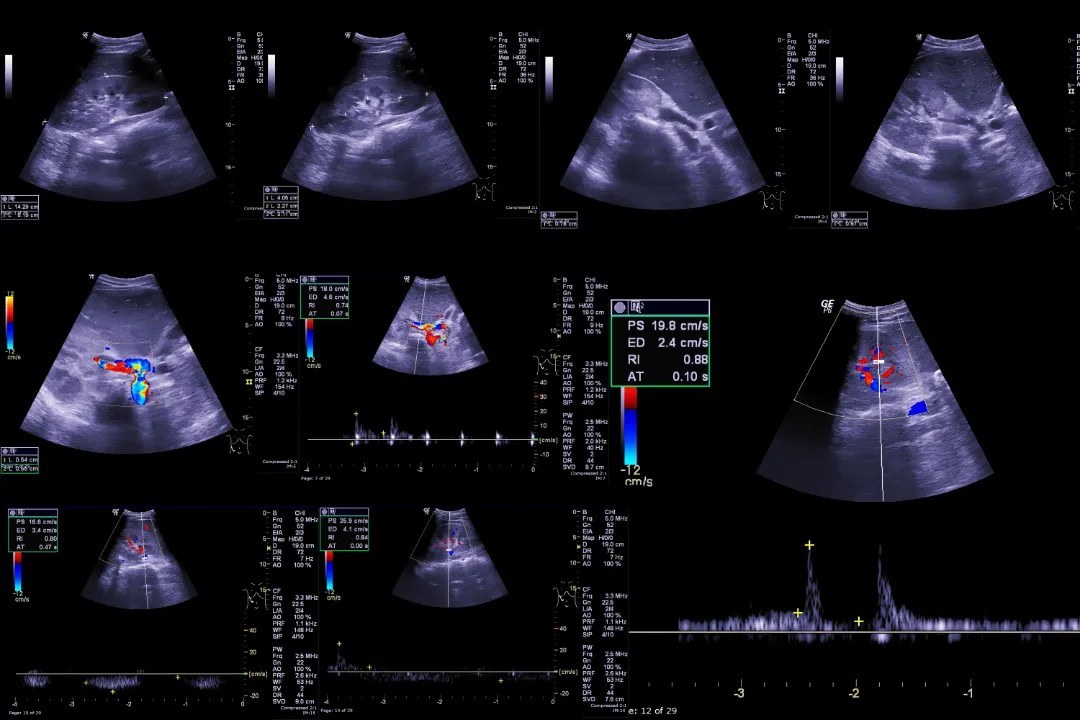

Hepatobiliary US Imaging Illustrations International Emergency What Is A Nm Hepatobiliary Test Hepatobiliary imaging is a type of nuclear medicine imaging that helps evaluate the liver, gallbladder, and the ducts that are part of the biliary system. It lets a healthcare provider look at the bile ducts, gallbladder, and liver. Nuclear medicine uses small amounts. While it can be stressful to have to. Hepatobiliary scintigraphy is a nuclear imaging technique that permits. What Is A Nm Hepatobiliary Test.

From iem-student.org

Hepatobiliary US Imaging Illustrations International Emergency What Is A Nm Hepatobiliary Test A hida scan, also called cholescintigraphy or hepatobiliary scintigraphy, is an imaging test used to view the liver, gallbladder, bile ducts, and small intestine. Hepatobiliary scintigraphy is a nuclear imaging technique that permits evaluation of the liver and biliary system for acute and chronic cholecystitis, biliary atresia, biliary. A hida scan (hepatobiliary iminodiacetic acid scan) is an important test for. What Is A Nm Hepatobiliary Test.